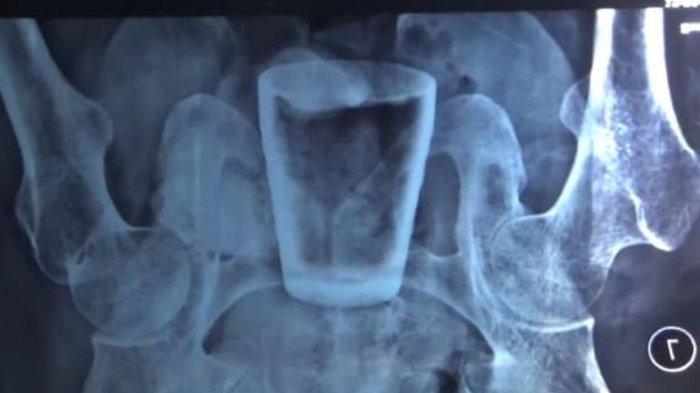

Ada Gelas Kaca dalam Tubuh Pria di Jember, Dokter Menduga Dimasukkan Lewat Anus

Ada gelas kaca di dalam tubuh seorang pria di Jember ini. Dokter menduga gelas tersebut dimasukkan dari anus.

Usut punya usut, di dalam tubuh Lasiadi terdapat sebuah gelas kaca yang sedikit pecah di bagian bibirnya.